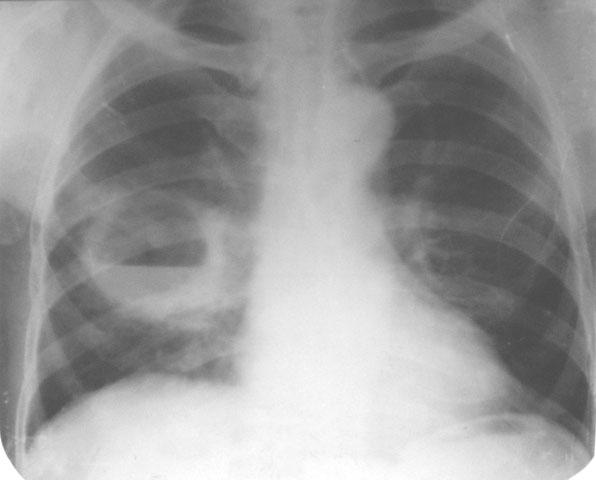

Рентгенологические изображения и синдромы патологии легких

Раздел: Кадры-подсказки